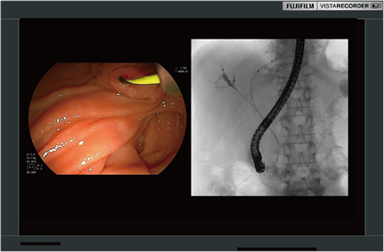

録画範囲のトリミングにより、内視鏡画像も透視画像も大きくPinP録画。特に内視鏡と透視を1:1で録画するときに役立ちます。

ERCP